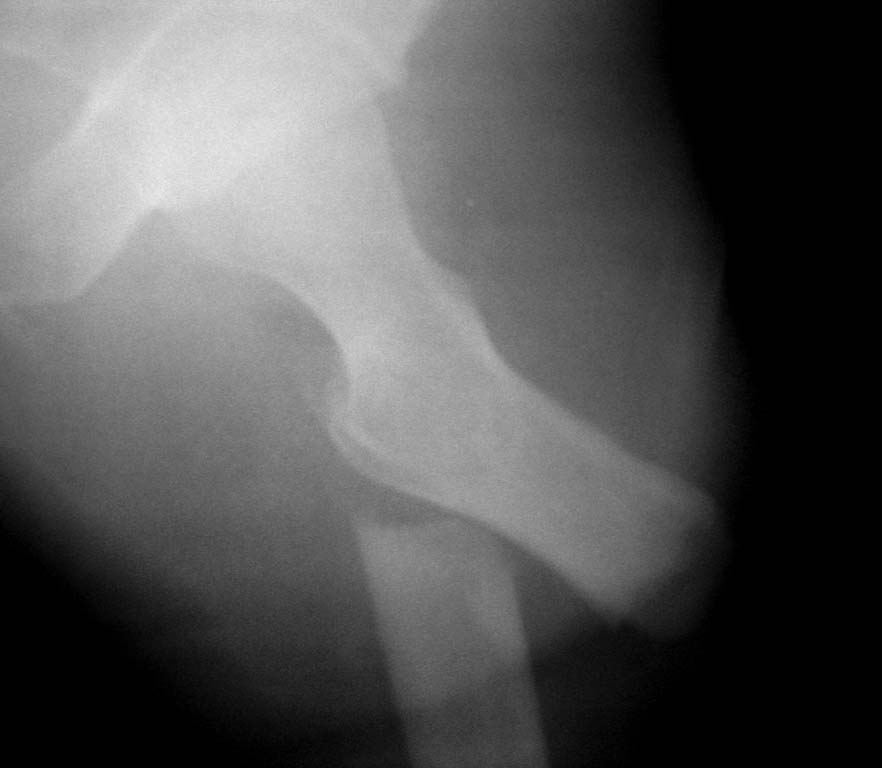

Нужен совет. Открытый перелом в\3 диафиза с оскольчатым переломом дистального метаэпифиза бедра. Закрытый оскольчатый внутрисуставной перелом проксимального отдела большеберцовой кости той же конечности.При поступлении ПХО ран, скелетное вытяжение. Рана зажила первичным натяжением. Осложнилось правосторонней пневмонией. Предстоит выбрать тактику оперативного лечения и камими имплатнатами.По нашему мнению случай нестандартный, требуется обсуждение коллег.

Уважаемый,Harisych. Интересное вытяжение у вас через перелом и недовесом груза, обратите внимание, или не называйте его скелетным вытяжением. Лечение всех переломов с помощью аппарата Илизарова.